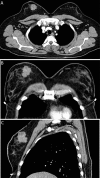

Lymphoepithelioma-like carcinoma of the breast is a rare malignancy, with fewer than 20 cases documented in the literature. Given the paucity of reported cases, there is limited information available to guide the diagnosis and management of patients with this tumor. We present a case of a 39-year-old woman with a palpable right breast mass that was initially diagnosed by core needle biopsy as infiltrating carcinoma with prominent lymphoplasmacytic stroma. Subsequent neoadjuvant chemotherapy with docetaxel, doxorubicin, and cyclophosphamide resulted in a marked decrease in the size of the mass. After wide local surgical excision, pathology revealed a lymphoepithelioma-like carcinoma of the breast. Given the excellent treatment response, our experience may help clinicians determine future therapeutic strategies for this rare breast tumor.